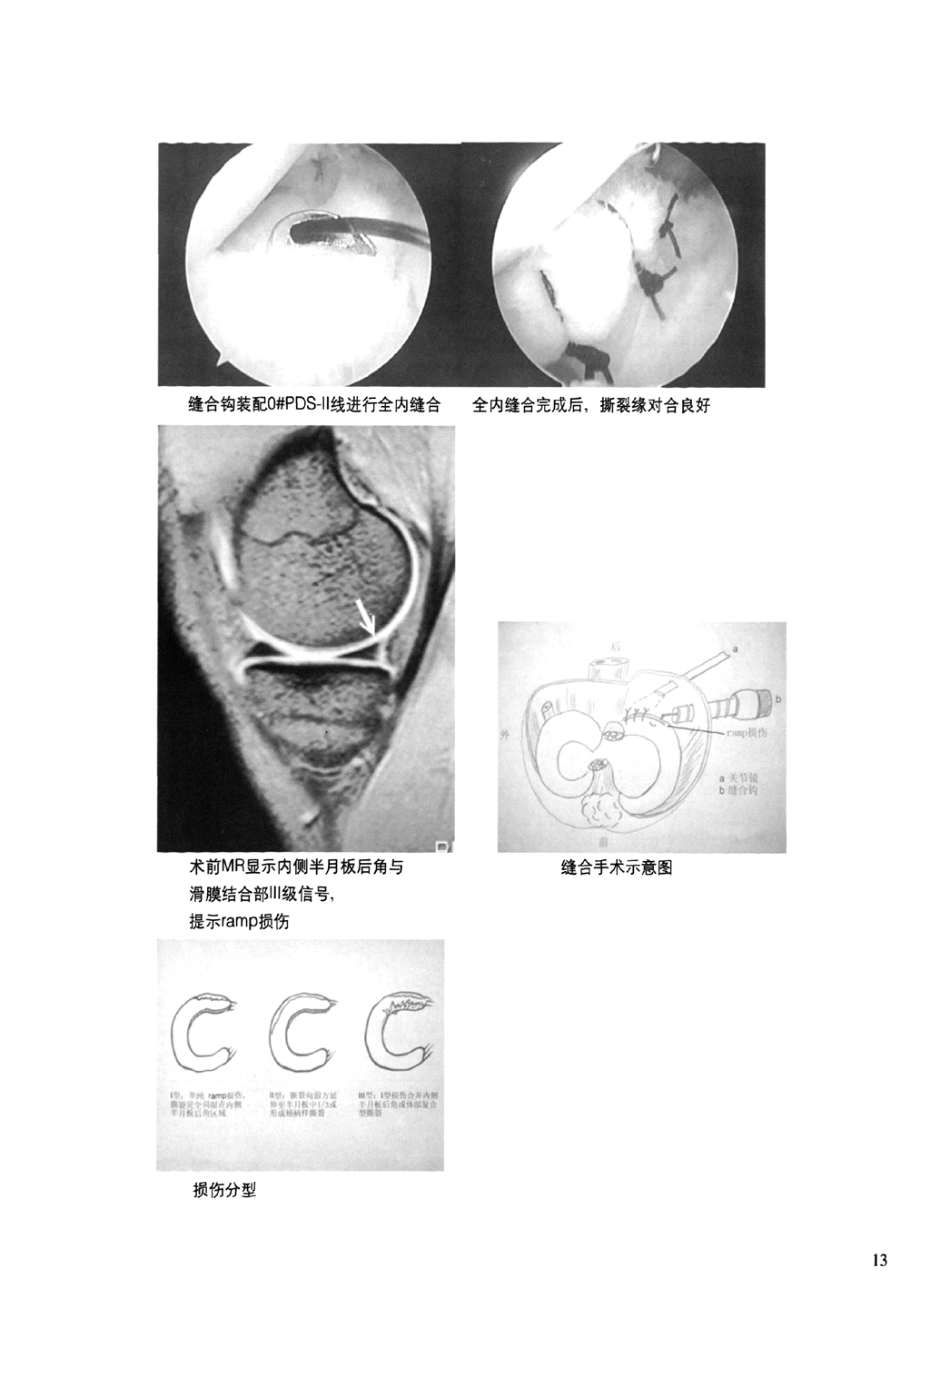

关节镜下半月板缝合新技术全内缝合法修补内侧半月板后角损伤北京积水潭医院运动医学中心冯华洪雷耿向苏张辉膝关节内侧半月板后角损伤(posteriorhornmedialmeniscus,PHMM)是一种非常多见的运动损伤,有很多种损伤类型,其中,内侧半月板后角靠近滑膜边缘的撕裂,是较为特异的一种,多见于陈119的、病程长的前交叉韧带(AnteriorCruciateLigament,ACL)损伤,又称ramp损伤。据Indelicato统计:63%的ACL损伤合并此种ramp损伤,陈IE]ACL损伤的合并发生率更高。膝关节内侧半月板后角与滑膜的结合部分称为ramp区域,位于膝关节后内间隙。由于常规的前方关节镜入路难于观察到,所以常被关节镜医生称为盲区,ramp损伤也因而经常被忽视。即使得以发现,也由于无法采用常用的半月板修补缝合方法而放弃治疗,形成“技术性忽略”。未经治疗的ramp损伤不会自然愈合,如果进一步发展,一方面可以继续向前方纵形延伸,形成更大的桶柄样撕裂,另一方面可以形成局部的复合性撕裂,造成整个半月板或后角的不稳定。不仅如此,未经修补的内侧半月板后角失去了保护ACL移植物的重要作用,使得移植物过度承担33—50%的不良负荷。因此,当重建ACL时,应尽可能修补内侧半月板后角。一、术前诊断术前症状:I型的ramp损伤没有明显的临床症状,II型及⋯型的ramp损伤可表现为交锁,别卡,伸膝受限。陈IRACL损伤表现为明显的膝关节不稳定,患者主诉经常运动时扭伤患膝,不能用患膝作支持腿进行各种动作,如急转身,急停,单腿跳等。急性ACL损伤表现为肿胀,活动受限等急性期症状。术前体征:I型的ramp损伤没有明显的临床体征,Il及⋯型的ramp损伤存在关节伸直受限,内侧关节间隙固定压痛,McMurray试验阳性等体征。ACL损伤可引出Lachman试验及轴移试验阳性。术前MRI检查:所有病例均常规进行。通过矢状位T1或PD序列(我院采用FFE序列,phillip1.0MRI)观察内侧半月板后角的滑膜移行区域,如果观察到半月板与滑膜分离征象,即可诊断ramp型损伤。对于JI型及川型,从冠状位及矢状位序列可观察到内侧半月板后角的⋯级高信号,如果出现特异的“双后交叉韧带征”,可明确诊断为“桶柄样撕裂”。但MRI诊断I型ramp损伤有一定比例的假阳性及假阴性,需要关节镜检查明确诊断。分型:根据撕裂特点进一步将损伤分为三种类型:I型为单纯后角损伤,撕裂完全局限在内侧半月板后角区域;Il型为l型撕裂向前方延伸达到半月板中1/3区域或桶柄样撕裂;⋯型为I型合并内侧半月板后角或体部的复合型撕裂。二、手术方法1.关节镜检查与入路:建立标准的前外(anterolateal,AL)及前内(anteromedial,AM)关节镜手术入路。关节镜自AL入路置入后,屈膝60。一90。位,蚊式止血钳钝性分离髁问窝内侧壁与后交叉韧带之间的间隙,建立经髁间窝入路(transcondylarportal,TC)。通过AL与TC入路将关节镜置入膝关节后内间隙,观察ramp区域,同时利用18#硬膜外穿刺针芯经皮穿刺探察,即可明确诊断。建立后内侧入路:通过AL与TC入路将关节镜置入膝关节后内间隙,在关节镜监视下,于膝关节后内侧间隙作相距2—3Cm的高位后内(hghposteromedialportal,HPM)及低位后内(10wposteromedialportal,LPM)两个入路,分别置入直径7.0mm及5Omm两个工作套管。HPM人路用于关节镜观寮、LPM^路作为缝台通道Tc与AL八路作为引线通道。2ramp损伤全内缝台方法。关节镜自HPM八路进行观察、刨刀或半月板锉自LPM^路置八,充分打磨清理半月板厦滑麟撕裂边缘。选择左向或右向缝台钩(SuturehooK/CorkscrewLinvatecLargo,FL)并装配O#PDS11可吸收缝台线(EthiconSomerville.NJ)。缝台白视野远倒(即靠近后交叉韧带处)向近侧(即靠近八路)进行缝台。缝台钩应首先穿过滑膜倒、钩的尖端自裂缘伸出,尽量向二方提升滑膜,然后再缝台半月板侧裂缘,保证撕裂缘对台良好,关节镜探钩RTCA,路置^顶压半月板辅助缝台钩进行缝台将缝线的一端通过TC与AL八路暂s出体外,撤出缝台钩.使用夹线钳(sutureretrieverLinvatecLargoFL)将两线端同时引出LPM.^~路。缝台时也可借助缝线引导丝(shuttlerelayLinvatecLargo.FL)拉拢缝台更多的组织或进行多重撕裂的缝台。使用打结器(knotpusher,Linvatec.L...